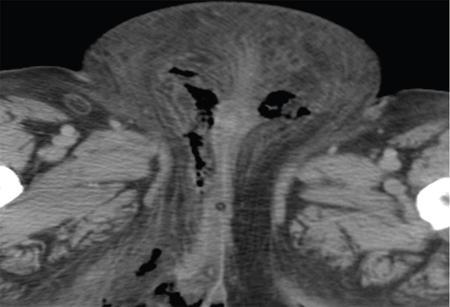

Kingston Vijay, Jansi Vinod, Sivakumar FOURNIER GANGRENE (NECROTIZING FASCIITIS): AN INFREQUENT TISSUE EATING DISEASE Fournier’s gangrene (FG): An awful infection of the visible genital region that causes grievous pain in the perineal area, which progresses from erythema to necrosis of tissue. FG is an acute dreadful urologic emergency, which has a high mortality rate of 15%–50%. It is a swiftly advancing, polymicrobial necrotizing fasciitis of the perineal, perianal and genital regions, which leads to reduced local blood supply causing vascular thrombosis in the skin and subcutaneous tissues. Subsequent spread of bacterial infection ensues with transfascial spread leading to development of gangrene of the overlying tissues. Fascial necrosis occurs at a rate of 2–3 cm/hr, making early diagnosis pivotal. Early diagnosis is essential and warrants surgical debridement and antagonistic triple antibiotic therapy. Computed tomography (CT) helps to confirm the diagnosis in clinically doubtful cases. In addition, radiography or ultrasound (US) can denote certain useful findings of FG, but CT has greater specificity for the diagnosis and displays the disease extent. Every radiologist must fathom out the imaging features of FG to document accurate diagnosis and urgent surgical treatment. FG is an acute terrible necrotic infection of the scrotum, penis and perineum. It is manifested as scrotal pain and redness with expeditious progression to gangrene and sloughing of tissue. FG is habitually secondary to perirectal or periurethral infections associated with local trauma, lower urinary infection and other operative procedures. The primary focus is located in the genitourinary tract, lower gastrointestinal tract and in the skin. FG is caused by both aerobic and anaerobic bacteria. It can eventually lead to multiple organ dysfunction syndrome (MODS) and death in severe cases. Owing to the dreadful complications, it is crucial to diagnose FG as quickly as possible. In spite of the antibiotics and surgical debridement, the death rate of FG remains high. It was first reported by Jean Alfred Fournier, who was a French professor of dermatology at St. Louis venereal hospital, the University of Paris in 1883. He observed a necrotizing gangrenous infection of male genitalia in young healthy males without any apparent source. The perineum is the area referring to the shallow internal compartment and external surface of the body (Fig. 11.11.1.1). The compartmental area of perineum is seen inferior to the pelvic outlet and is divided from the main pelvic cavity by the pelvic diaphragm. This pelvic diaphragm holds up the urogenital and gastrointestinal systems and plays an important role in defecation, micturition, sexual intercourse and labour. When viewed in subject with abducted thighs, the perineum resembles a diamond-shaped area that is bounded by the mons pubis anteriorly, medial aspect of the thighs laterally and the gluteal folds and upper end of natal cleft posteriorly and following osseofibrous boundaries: An imaginary transverse line connecting the anterior ends of the ischial tuberosities splits the perineum into two triangles: It is located in the rear half of the perineum. The sacrotuberous ligaments, the coccyx and an imaginary line connecting bilateral ischial tuberosities bound it. The major contents are: The main nerve of the perineum, the pudendal nerve is located in the anal triangle. The urogenital triangle is the front half of the perineum. It is bounded by pubic symphysis, ischiopubic rami, and an imaginary line between the two ischial tuberosities. Urogenital triangle has number of fascial layers and pouches and complex. Dissimilar to the anal triangle, the urogenital triangle has an extra layer of strong deep fascia, which is called as perineal membrane. The membrane has pouches on the superior as well as inferior surfaces (Fig. 11.11.1.3). The layers of the triangle (deep to superficial) (Fig. 11.11.1.4): Is located on the midpoint of theoretical transverse line joining the ischial tuberosities that is providing attachment to the perineal muscles. Perineal body lies deep to skin and subcutaneous tissue in the midline at the junction of anal and urogenital triangles. It is seen behind the vestibule of the vagina or bulb of the penis. Anus and anal canal are seen behind the perineal body. The perineal body is varying in size with little fat deep to the overlying skin (Fig. 11.11.1.6). All the perineal muscles converge in the perineal body and have three stratum. Superficial stratum includes bulbospongiosus, superficial transverse perenei muscles and superficial part of external anal sphincter. Intermediate stratum includes sphincter urethrae and deep transverse perenei muscle and deep part of the external anal sphincter. Deep stratum contains levator ani muscle. It is a triangle-shaped musculofascial diaphragm situated in anterior half of the perineum located in the region of the urogenital triangle filling space of pubic arch. It is pierced by urethra in both male and female and vagina in females. It holds the prostate gland and it constricts the vagina. It has: Infection of superficial perineal fascia (Colles’ fascia) may spread to the penis and scrotum across the Buck and Dartos’ fascia. Infection can spread into the anterior abdominal wall along the Scarpa’s fascia. Colles’ fascia limits progression of disease as it is attached to the perineal body and urogenital diaphragm posteriorly and to pubic rami laterally. Testis is rarely involved, as the testicular arteries originate directly from aorta. Well-advanced FG can extend from the fascial envelop of the genitalia throughout the perineum, across the torso and upper thighs. The superficial perineal space receives its blood supply from the internal pudendal artery, which is the branch of the internal iliac artery. Pudendal nerve and its branches are supplying the superficial perineal space. The posterior labial nerve, which is a branch of pudendal nerve has a medial and lateral branch and runs along the lateral part of the urethral triangle to supply the skin of the labia majora. The posterior scrotal nerve, which is branch of pudendal nerve has a medial and lateral branch and runs along the lateral part of the urethral triangle to innervate the skin of the scrotum. FG usually not only involves the corpora, urethra, testes, cord structures and deep muscular structures, but also the superficial and deep fascia as well as the skin. The infection spreads along the anatomical fascial planes. So knowing the routes of spread, familiarity with the perineal anatomy and its fascial planes is very important in understanding the potential pathways of disease spread. Thus if the Colles’ fascia is interrupted, then the infection can easily spread to the ischiorectal fossa and subsequently to buttocks and thighs. Urethral stricture Scrotal abscess Epididymo-orchitis Hydrocele Surgery/Aspiration Traumatic catheterization Urethral calculi Prostatic biopsy Vasectomy Perianal abscess Rectal biopsy Anal dilatation Haemorrhoidectomy Rectosigmoid malignancy Appendicitis Diverticulitis Strangulated inguinal hernia Infected Bartholin’s gland Vulval abscess Septic abortion Episiotomy wound Coital injury Genital mutilation In FG, rotting bacterial infection can cause microthrombosis of small subcutaneous vessels bringing about gangrene of the overlying skin. Cultures of FG wound often show poly microbial infections by aerobes and anaerobes, which include: Nonuniformity in clinical presentation. From subtle onset and slow progression to swift onset and fulminant course. Symptoms of FG include scrotal oedema, hyperemia, fever, pain, pruritus and crepitus. Crepitus is a common feature because of the presence of gas under the skin. Air in the soft tissues is produced by anaerobic bacteria and consists primarily of nitrogen, hydrogen, nitrous oxide and hydrogen sulphide. FG infection starts as cellulitis then necrotic patches start appearing over the skin and progress to extensive necrosis. Leucocytosis, anaemia, thrombocytopenia, dehydration, tachycardia, hypocalcaemia, and hyperglycaemia are the systemic manifestations of FG. FG can rapidly progress to septicaemia and multiple organ failure. Involvement of the testis is very rare, which suggests retroperitoneal origin or spread of infection. The diagnosis of FG is usually clinical. Imaging has an ancillary role. Radiologic evaluation is indicated when the diagnosis is not clearly established. The goals of radiologic evaluation are: Radiolucent soft tissue gas shadow may be seen over the scrotal or perineal region. The subcutaneous air pockets can enter from scrotum and perineum to the anterior abdominal wall, inguinal regions and thighs. Soft tissue air pocket visualized on X-ray of diabetic patients with FG in 100% of the cases, while physical examination can pick up scrotal wall air pockets only in 29% of the cases. High-resolution linear transducer (5–15 MHz) imaging of scrotum is a helpful tool in the diagnosis of FG prior to the clinical suspicious or physical examination of the disease. Ultrasound scan can show widespread abnormalities of scrotum such as scrotal wall oedema/cellulitis, testicular torsion, acute epididymo-orchitis, testicular trauma, necrotizing fasciitis and an obstructed inguinoscrotal hernia. Ultrasound can also display a thickened oedematous scrotal wall, air shadows within the scrotal wall, paratesticular fluid collection. Presence of subcutaneous air pockets in the scrotal wall with unhealthy echogenic white after shadows is the sonographic hallmark of FG. This distinct sonographic appearance of scrotal wall air shadows is due to fluid–air interface. Often the testis and epididymis are normal in size and echotexture because of different blood supply directly from abdominal aorta through testicular arteries. An obstructed inguinoscrotal hernia may show the presence of air shadows within the bowel loops or within the scrotal sac but not in scrotal wall layers. Many times ultrasound scan depicts the presence of air pockets in nearby subcutaneous soft tissues other than scrotal wall before physical examination does. Distribution of soft tissue air pocket may indicate the extent of the disease in multiple fascial planes. Scrotal wall emphysema may extend into the perineum, inguinal region and abdominal wall and occasionally into the thigh. Absence of scrotal wall emphysema dose not excludes the diagnosis of FG. CT is a very valuable tool in diagnosing and determining the extent of FG. Clear knowledge of the anatomy of perineal region and fascial planes, the extent of the disease can be established to a degree more specific than is possible with physical examination/sonography. CT is the modality of choice in FG. CT findings include: CT scan dominates in the detection of deep-seated perineal, pelvic and intraabdominal fluid collections, which is very important in the eradication of the disease. It also provides wide field of view of perineum, pelvis and proximal portion of the lower extremities. Retroperitoneal extension is also well demonstrated with CT. Extent into anal triangle and urogenital triangle can be clearly made out. CT screening of perineum and pelvis can frequently show the underlying cause of the FG such as urethral pathology, perianal abscess, fistulous tracts, incarcerated hernia and source of infection that may be from intraabdominal or deep pelvic process and helping to planning of surgical debridement and management. Posttreatment follow-up CT scan is very important in assessing for improvement or worsening of FG. CT is useful in deciding additional therapy or surgical excision. MRI scan of the pelvis and perineal region is used to assess the extent of FG along the tissue planes. MRI yields better soft tissue details than the CT scan (Fig. 11.11.1.8). STIR imaging displays the oedema/inflammation of skin, subcutaneous fat and inter muscular planes as hyperintense shadows. Air loculi present in interstices of scrotal wall appear as hypointensities. MRI scan clearly demonstrates the extension of FG inflammatory process into the inguinal canal, pelvic cavity and in ischiorectal fossa as bright hyperintense shadows. Prolonged time for MRI scan, patient monitoring difficulties, clinically unstable patients limit the practical usefulness of MRI scan. The mortality in FG is little high ranging from 3% to 45%. Factors associated with high mortality include: Early presentation in good functional status along with appropriate and timely treatment leads to a good outcome. FG wound extending more than 5% of the body surface area carries a poor prognosis. Abdominal wall or lower limb involvement has notable increase in mortality rate. Used for prognostication and predicting mortality probability in FG. This is a numerical score derived from a combination of nine physiological variables including temperature, respiratory rate, heart rate, creatinine, sodium, potassium, bicarbonate, white cell count and haematocrit. FGSI score more than 9 indicates 75% mortality probability while less than 9 indicates a 78% survival probability. FG is an infrequent but quickly growing disease that mostly affects men with certain comorbid risk factors. In spite of all advances in medical care, it still continuous to be a disease with high mortality. The early debridement of necrotic tissue is the paramount factor for survival. ABDOMINAL WALL HERNIA Hernia refers to the protrusion of a part or structure through the tissues normally containing it through either through stretching or opening in normal tissues. Hernia may be external/internal. Hernias are the frequent imaging findings in abdomen. Most are asymptomatic but chances of developing complications present like incarceration, strangulation and trauma are present, so often they are surgically repaired. Using linear 10 MHz transducer inguinal region is examined. In obese patients 7 MHz may be required. During Valsalva, manoeuvres characteristic movement of herniating tissues through the defect clinches the diagnosis. This dynamic imaging is the added advantage in ultrasound. If bowel is the content peristalsis noted. If fat is the content in the sac, it appears hyperechoic. BOX 11.11.2.1 CLASSIFICATION OF EXTERNAL HERNIA

CT scan